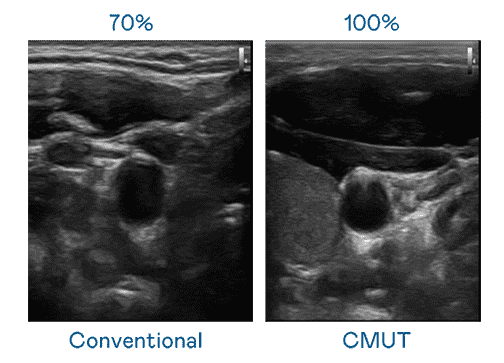

CMUT 技术是一种用电容式微机电元件来产生超音波讯号的技术。。与传统 PZT 压电式技术相比,,,CMUT 频宽增加 30%,,,,更宽频的超音波讯号让影像解析度大幅提升,,是实现高影像品质医疗超音波扫描、、促进精准医疗发展的关键技术。。。

大频宽带来超清晰影像

超音波影像的解析度高低,,首先取决于探头能发出的讯号频宽。。28国际 CMUT 可提供高清晰的超音波讯号,,,提供高频宽、、、高灵敏度、、、、影像纹理细节更高的超音波影像,,协助医护人员缩短影像判读时间及利用精准的医疗影像进行诊断。。